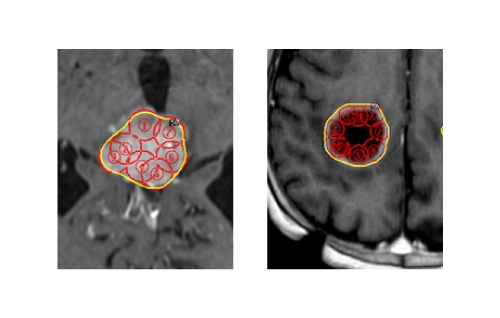

ガンマナイフの治療目的

できる限り 正常脳組織を傷めず、腫瘍の成長止めるガンマナイフとは、ガンマ線を腫瘍細胞に集中照射し、細胞内の遺伝子(DNA)を切断するための治療。0.1mmの精度にて、周囲脳組織へ高い放射線量が当たらないよう安全を守ることができる、脳神経外科治療において、最も安全に治癒へ至らしめる可能性が高いのです(図2)。

図2:各球状照射野を腫瘍のみに配置し、脳への過照射を避ける

転移性脳腫瘍に対するガンマナイフ治療計画(図2)

最近では腫瘍外部への過照射をなるべくしないように工夫しています。これにより、脳浮腫の発生が防御できる可能性が高くなっています。また、腫瘍内部をより高く照射できる工夫をしています。これにより、腫瘍栄養血管をつぶし細胞壊死にさらに追い込む努力をしています(図2)。